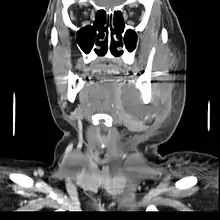

A dental infection resulting in an abscess and inflammation of the maxillary sinus

CT scan showing a large tooth abscess (right in the image) with significant inflammation of fatty tissue under the skin